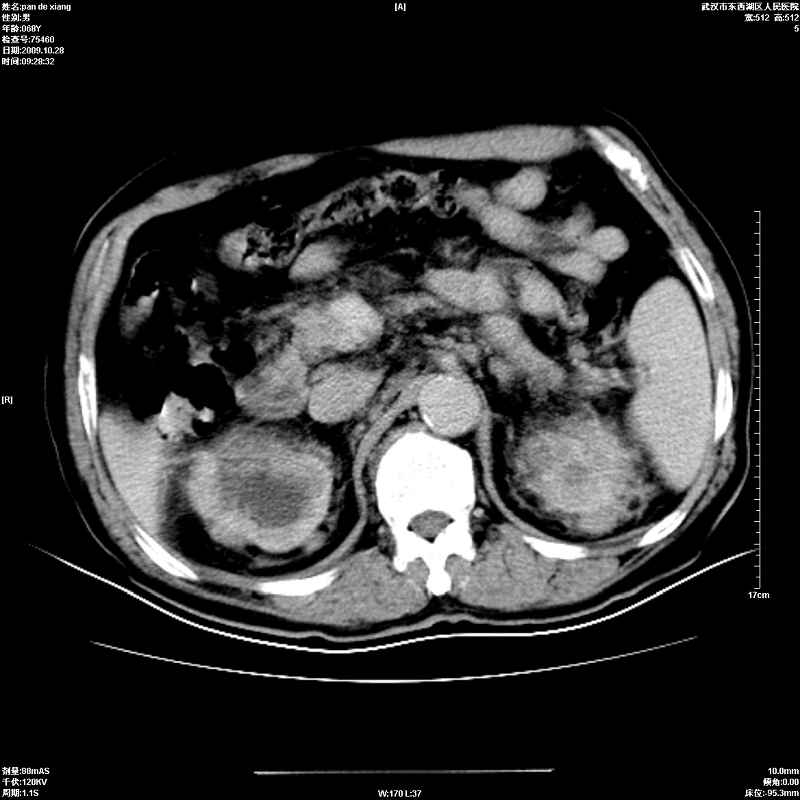

以下是引用杀毒软件在2009-10-28 20:41:00的发言:[br]结合临床考虑---白血病双肾改变或淋巴瘤。

以下是引用zxl51642在2009-10-29 9:59:00的发言:[br]结合临床“单克隆免疫球蛋白血症”,考虑双肾为继发损害并肾功能不全(尿中大量igg及少量iga、igm等大分子免疫球蛋白滤出所致继发损害),椎前软组织肿块为髓外造血。与浆细胞瘤有区别,平扫时有战友说的很清楚。